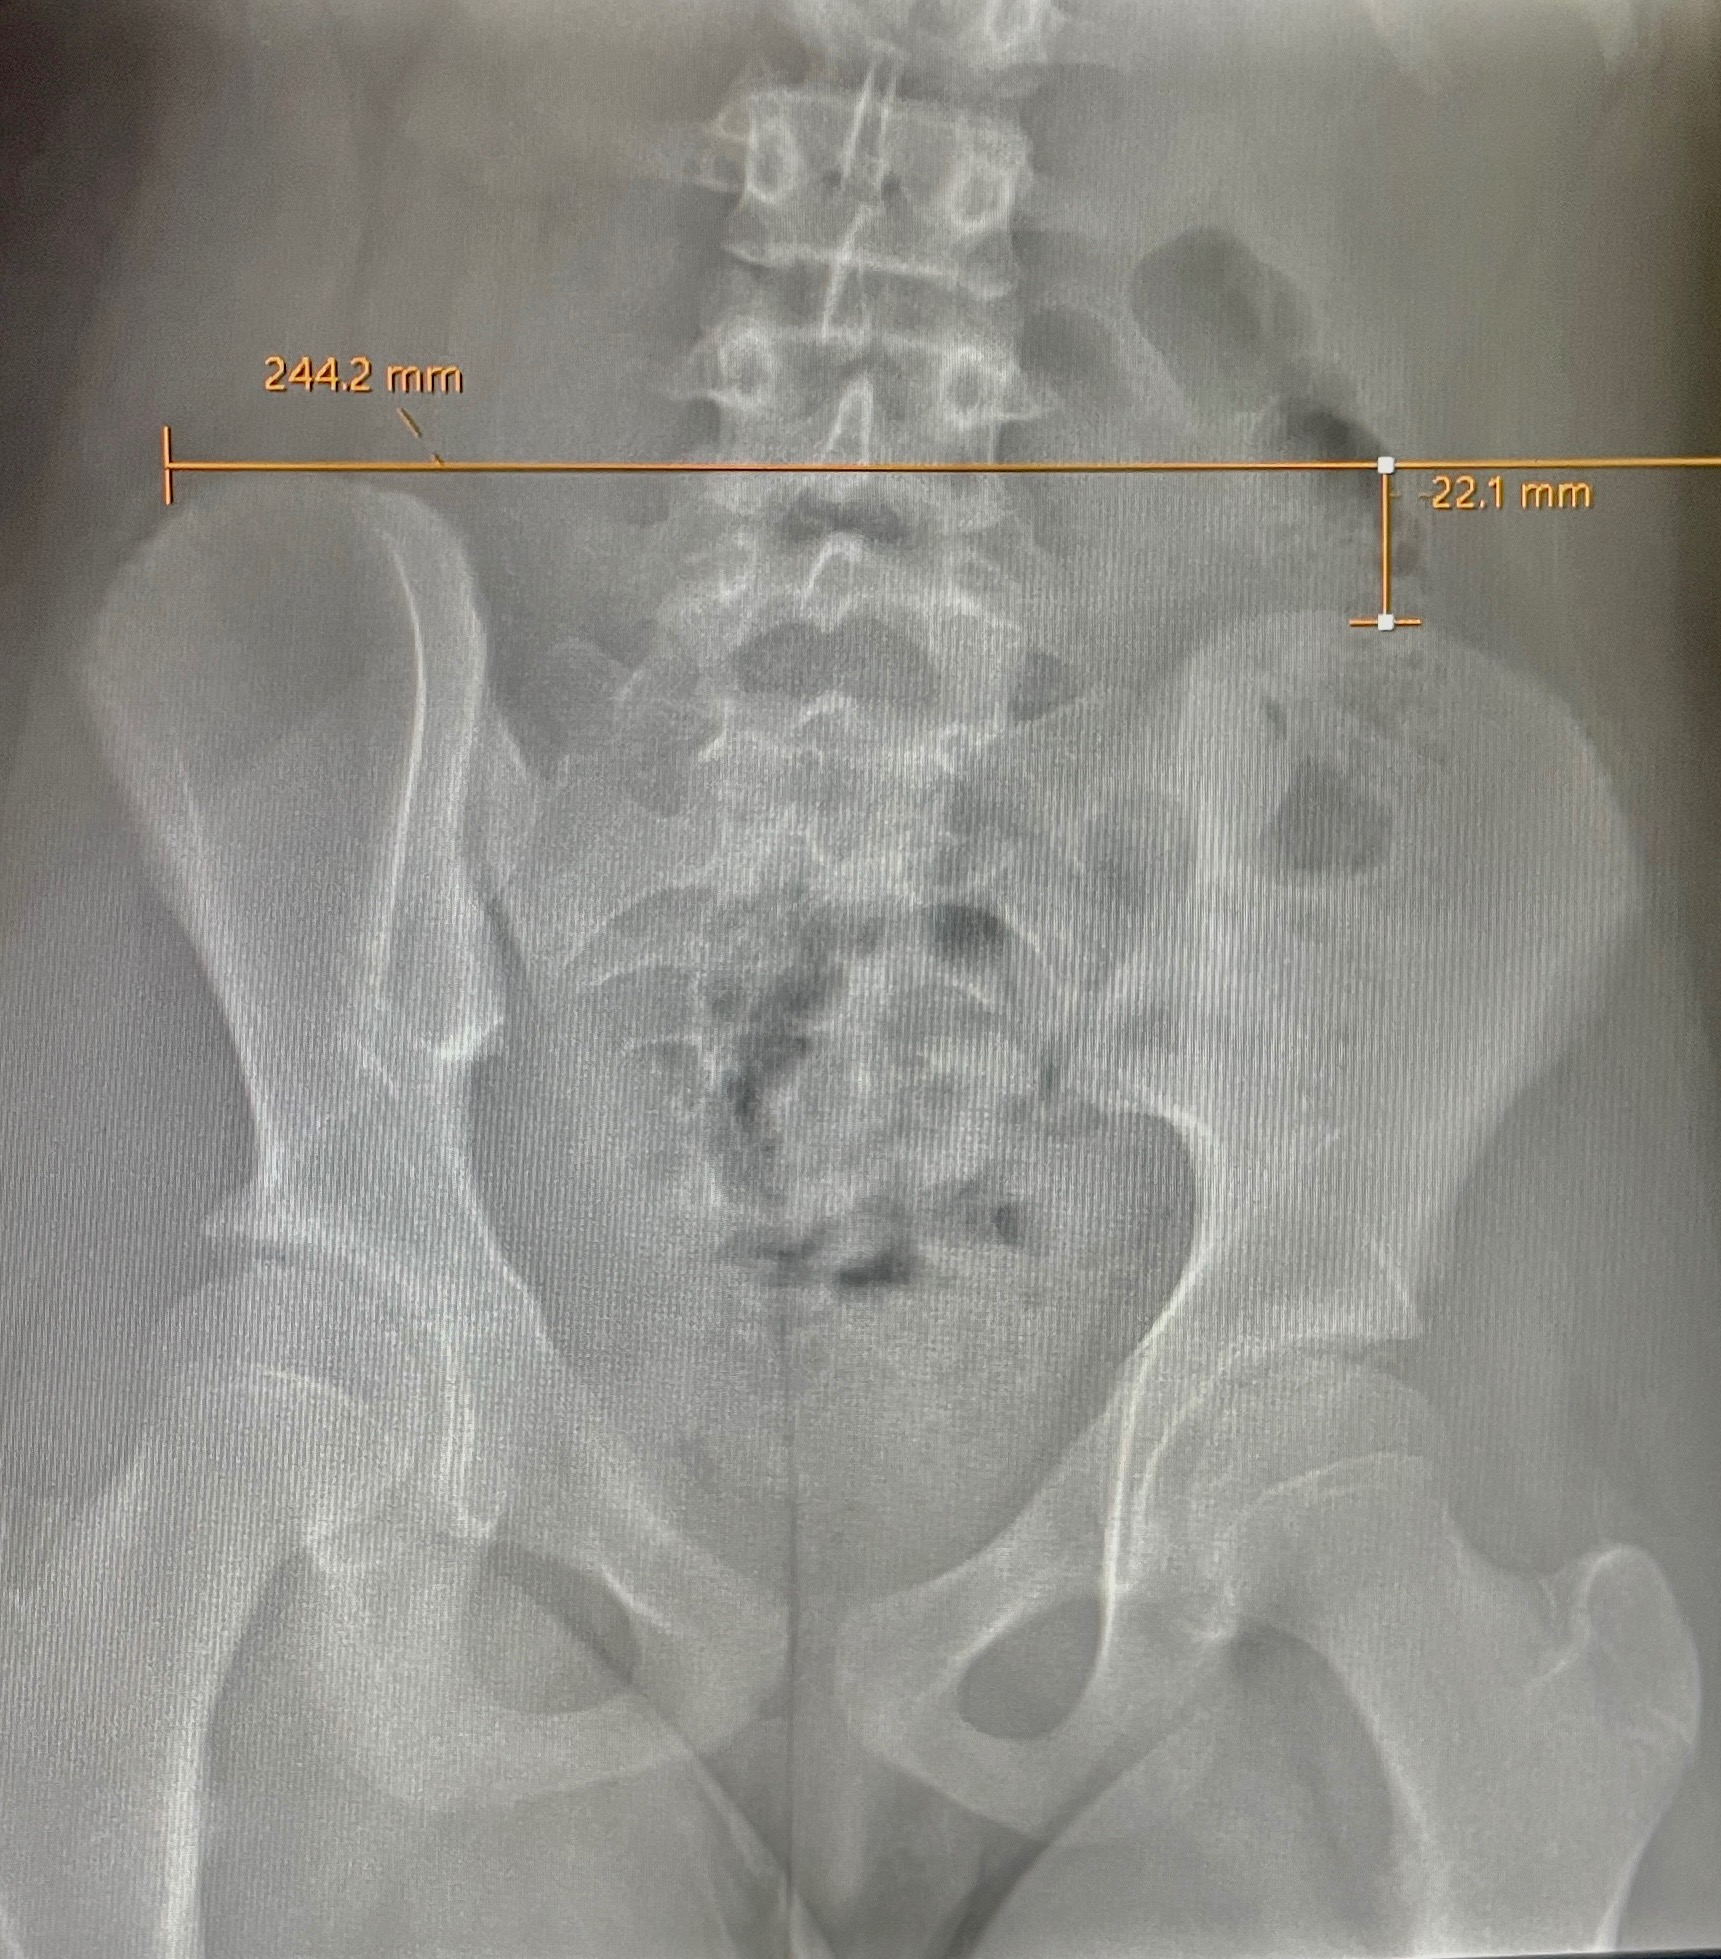

Amira is a passionate dancer, cheerleader, pageant competitor, and contortionist with scoliosis. Diagnosed at 9 years old, she was placed under a “wait and see” plan with her pediatric orthopedic team. Unfortunately, her condition has rapidly worsened and progressed to an S-shaped spinal curve measuring 38degrees. Additionally, she has a knee-length discrepancy caused by her scoliosis that is further complicating her condition.

To slow the progression and avoid an invasive and very costly spinal fusion surgery, Amira will need to wear a specialized brace until she’s done growing and undergo a noninvasive knee surgery. This treatment will preserve her ability to move freely and continue pursuing the activities she loves. However, our insurance does not cover the brace, even though it's considered medically necessary; the total cost we are responsible for is $5,000